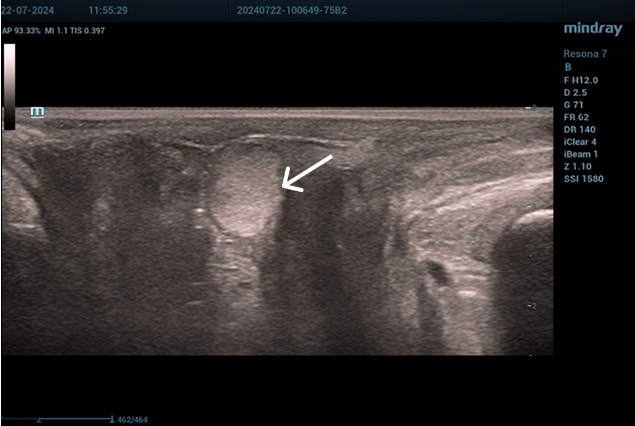

Эхограммы периуретральной области

Трансперинеальный доступ, линейный датчик.

Слева от уретры округлое образование с четкой капсулой и мелкодисперсной взвесью размерами 1,5×1,0 см (филлер с воспалением), справа — анэхогенное овоидное образование (филлер).

Эхограмма 2